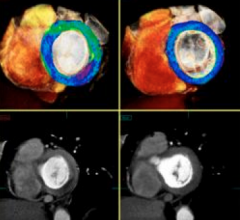

Cardiac computed tomography angiography (CCTA) is known to have excellent anatomical imaging, but has lacked the ability for functional assessments, requiring chest pain patients with intermediate stenosis lesions to be sent to the cath lab or nuclear myocardial perfusion imaging. However, recent advances in CCTA image analysis software and the accumulation of supporting clinical data may soon enable CT perfusion imaging and virtual fractional flow reserve-CT (FFR-CT) to become mainstream in the coming years.

Trends and new technology for cardiac computed tomography angiography (CCTA) were highlighted during the 2012 Society of Cardiovascular CT (SCCT) annual scientific meeting in July in Baltimore, Md. Major topics included the development of fractional flow reserve (FFR)-CT imaging, perfusion imaging, imaging for transcatheter aortic valve replacement (TAVR) and analysis software advancements.